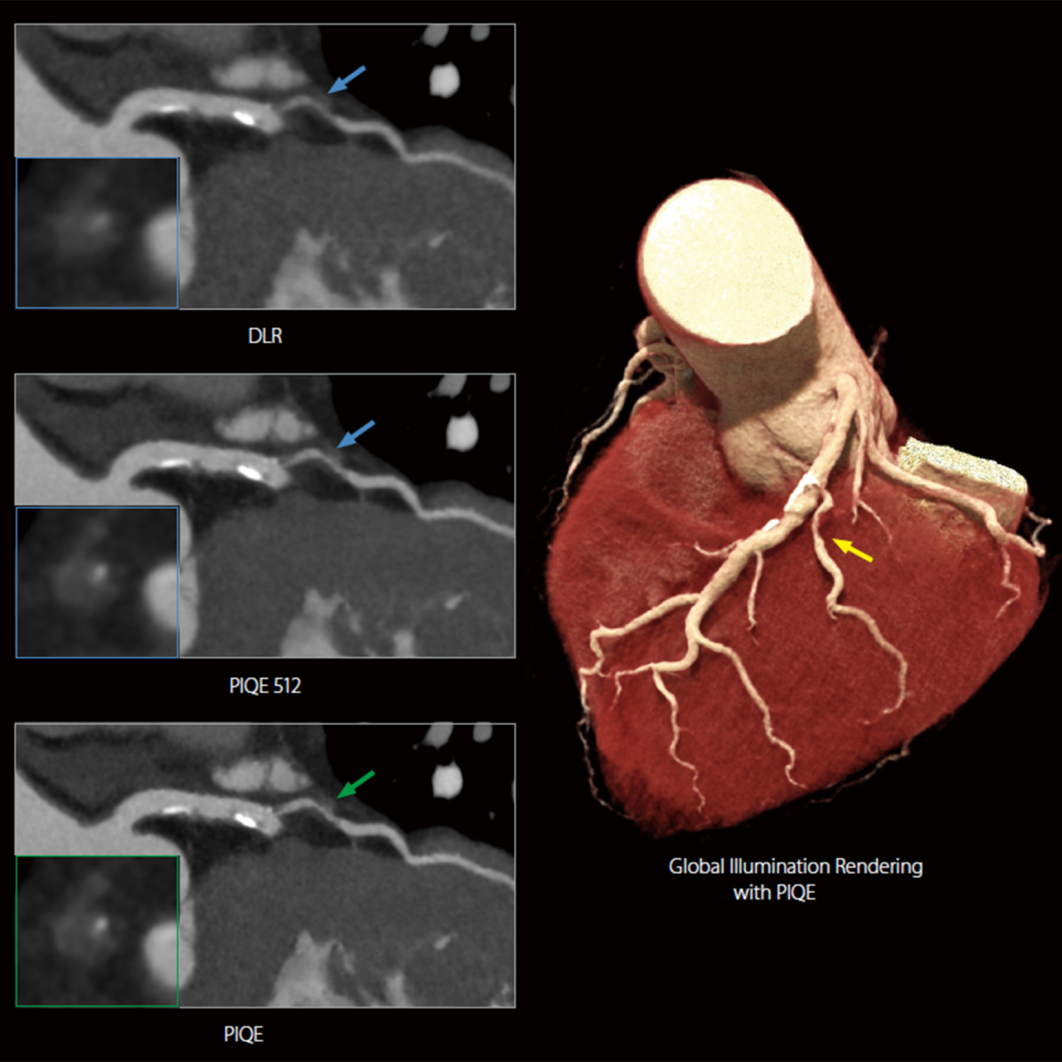

PIQE for CT

突破传统心脏成像限制

对分辨率的追求驱动着CT技术的进一步发展。一方面是聚焦硬件的探测器革新,例如0.25mm的超薄探测器切割、光子计数探测器等;另一方面,则是通过图像重建算法的辅助来实现,例如从传统的FBP到迭代算法、再到如今的深度学习重建算法。而佳能医疗将AI图像技术与宽体探测器深度融合,将CT图像分辨率提升至了新高度。

基于佳能医疗的深度学习神经网络平台,结合Aquilion Precision 4K级高清数据采集平台进行训练,得到高清AI引擎PIQE。结合宽体CT平台,PIQE可以同时提升图像分辨率和覆盖宽度,实现任意心率及心律不齐下的高清心脏成像,尤其有利于对心血管支架和斑块的显示。

基于百余年创新培育起来的影像技术积淀,佳能医疗在人工智能领域早已成果显著,早在2018年,我们就推出了用于提升CT图像质量并同时降低辐射剂量的高信噪AI引擎DLR-AiCE(Advanced intelligent Clear-IQ Engine),将CT图像质量提升至新的“视界”,如今,我们的AI影像技术已经创新迭代至PIQE,并实现跨产品应用于多个产品线,持续在全球的临床和科研探索中投入使用,不仅助力医疗一线危急重症的攻关,也将先进医疗资源带给了更多人群。